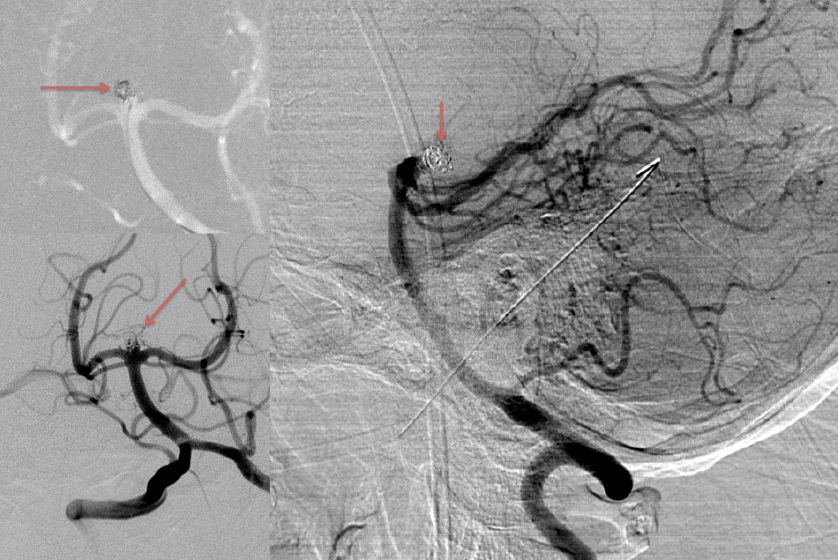

Urgent Cerebral Angiography confirmed a 5 mm posteriorly projecting aneurysm of the Basilar Artery Apex (Figure 2 A, B). Based on the location, morphology, and posterior projection, we decided to proceed to coil embolization of this high-risk aneurysm to prevent catastrophic re-bleeding and afford us the opportunity to maximize critical care for this patient during his hospital course. In this aneurysm, the dome-neck ratio was favorable from primary coiling, which was successfully performed resulting in near-complete embolization of the aneurysm (Figure 3 A, B). After 2 weeks of continued critical current l, endovascular, and neurosurgical care for complications of subarachnoid hemorrhage, including vasospasm and hydrocephalous, he was able to make a complete recovery and ultimately discharged home to complete his recovery, having regained all neurologic functions and activities of independent daily living and planning a return to work as an executive professional in the near future.

Figure 2: A) AP DSA angiogram demonstrates a 5 mm posteriorly projecting aneurysm of the Basilar Apex B) 3D DSA confirms the morphology and favorable dome to neck ratio for primary coil embolization.